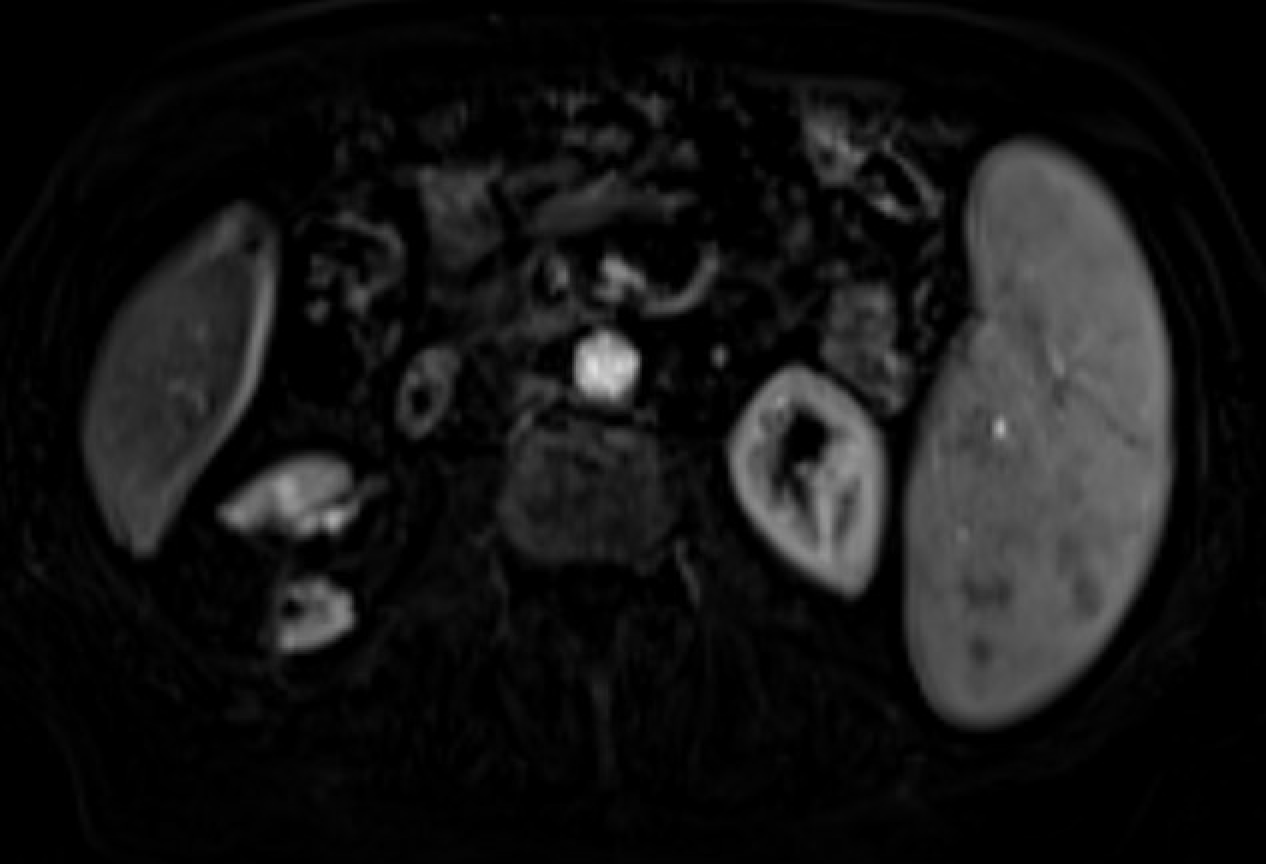

Follow-up MRI demonstrating no residual enhancement within the ablation zone after renal mass cryoablation — consistent with complete ablation and treatment success.